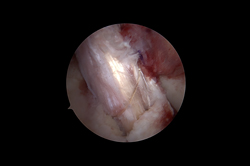

Arthroscopy - ACL Reconstruction, Maniscus Injury